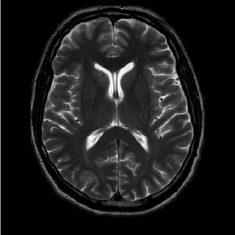

(b) FLAIT brain

Refer to caption

Figure 2: Test Images.

We turn now to test TDIHT for high dimensional signals. We test the performance of several MRI images: the Shepp-Logan phantom, FLAIT brain image, T2 Sagittal view of the lumbar spine and the circle of Willis. The first image is of size 256×256256256256\times 256, while the other are of size 512×512512512512\times 512. They are all presented in Fig. 2.

We focus on the recovery of these images from a few number of Fourier measurements. With 𝛀𝛀{\mathbf{\Omega}} set to be the undecimated Haar transform with one level of resolution (redundancy four) and 𝐃𝐃\mathbf{D} its inverse transform, we succeed to recover the phantom image using only 181818 sampled radial lines, which is only 6.5%percent6.56.5\% of the measurements. This number is only slightly larger than the number needed for GAP, relaxed ASP (RASP) and Relaxed ACoSaMP (RACoSaMP) in [10, 38]. The advantage of TDIHT over these methods is its low complexity as it requires applying only 𝐌𝐌{\mathbf{M}} and its conjugate and 𝛀𝛀{\mathbf{\Omega}} and its inverse transform while in the other algorithms a high dimensional least squares minimization problem should be solved. Note also that for AIHT and RAHTP the number of radial lines needed for recovery is 353535 and for IHT (with the decimated Haar operator with one level of resolution) we need more than 505050 radial lines.